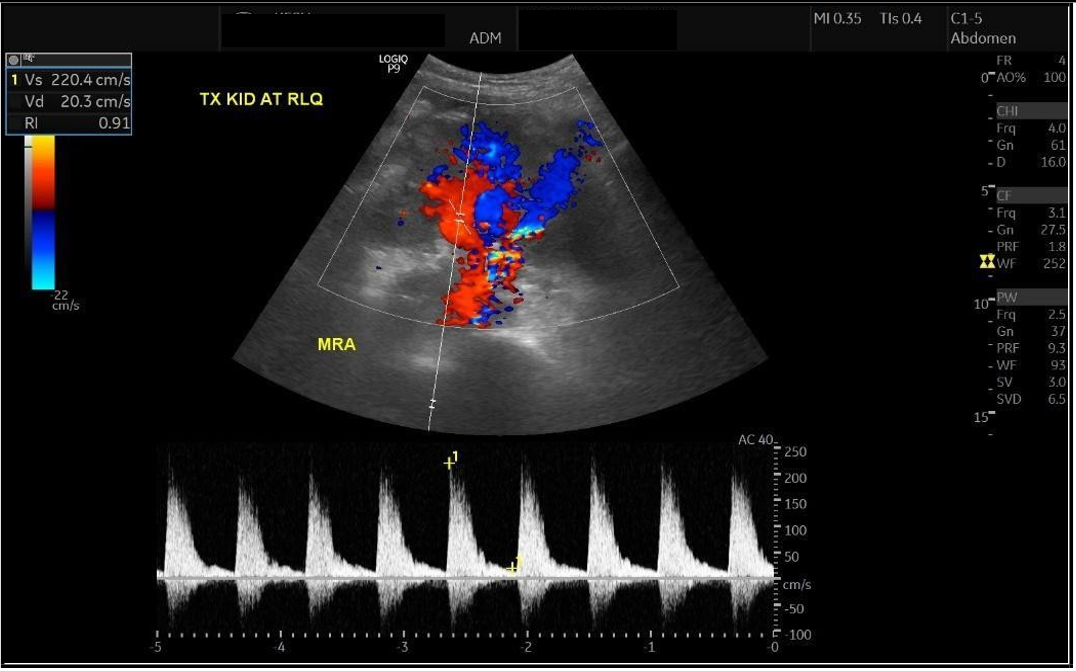

Upon presentation to our emergency department, her vital signs were notable for hypertension (BP 216/118 mmHg) and tachycardia (HR 109 bpm), though she remained afebrile and maintained oxygen saturation of 100%. Physical examination revealed ecchymosis over the right lower quadrant at the surgical site. Laboratory investigations showed severe anemia (Hb 7 g/dL), thrombocytopenia (66 × 10⁹/L), and serum creatinine (68 µmol/L). Abdominal ultrasound demonstrated preserved perfusion of the graft with patent main renal vessels. However, there was a significant increase in resistive index (RI) values within the intrarenal arterial branches, with areas showing a monophasic wave pattern, suggestive of impaired intrarenal flow and warranting close follow-up [Figure 1]. Additionally, elevated velocity at the main renal artery anastomosis site was noted, likely reflecting postoperative changes. A peri-graft fluid collection was identified, with the largest pocket measuring approximately 74 mL, requiring ongoing monitoring for potential complications.

Figure 1: Doppler showing elevated intrarenal resistive index with monophasic waveforms, suggesting impaired intrarenal flow (RI = 0.91).

Despite this, graft perfusion remained satisfactory, with a patent main renal artery and vein. Peak systolic velocities were measured as follows:

1. Pre-anastomosis: 140 cm/s

2. Post-anastomosis: 131 cm/s

3. At the anastomosis site: 366 cm/s

These findings suggest post-anastomotic turbulence, possibly reflecting vascular remodeling or narrowing, though without evidence of critical stenosis. The interlobar and arcuate arteries demonstrated normal waveforms, with resistive index (RI) values ranging from 0.68 to 0.82, slightly elevated compared to prior values (0.62–0.74), but still within acceptable limits for post-transplant surveillance.